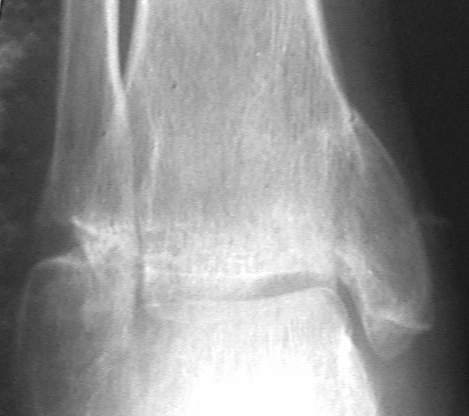

У больного травма в августе 2001 г. Лечился консервативно, Проводилась иммобилизация гипсовой лонгетой 3 мес. В последующем местное лечение. Остается контрактура боли в области наружной лодыжки. Направлен в наше отделение в конце января 2002 г Планируется костная аутопластика, остеосинтез пластиной, винтами перелома наружной лодыжки. Решается вопрос о коррекции неправильно сросшегося перелома внутренней лодыжки. Рентгенограммы: фас; профиль; план Сергей Зырянов

Кто сказал, что это ложный сустав (какой?) лодыжки?

Перелом сросся, другое дело что с небольшим смещением - с варизацией - это естественно при смещении внутренней лодыжки кверху.

Насчет наружной лодыжки - не уверен, что вообще надо что-то делать.

на снимке, кстати, срезан ее дистальный отдел, и правильность взаимоотношений с таранной костью не оценить. Если они правильные - я бы присоединился к мнению об оставлении ее покое.

А вот укорочение внутренней, похоже, привело к натяжению дельтовидной связки и гиперпрессии в медиальном отделе сустава, и уже сейчас там

видно сужение щели. Так что есть смысл обратить внимание на ортопедическую профилактику деформирующего артроза.

Надо сделать компьютерную томография и объектизировать истинное состояние переломов лодыжек. Пока не видно подвывиха таранной кости, а ложный сустав внутренней лодыжки (я его не вижу)в основном не вызывает функциональных растройств в голеностопном суставе.